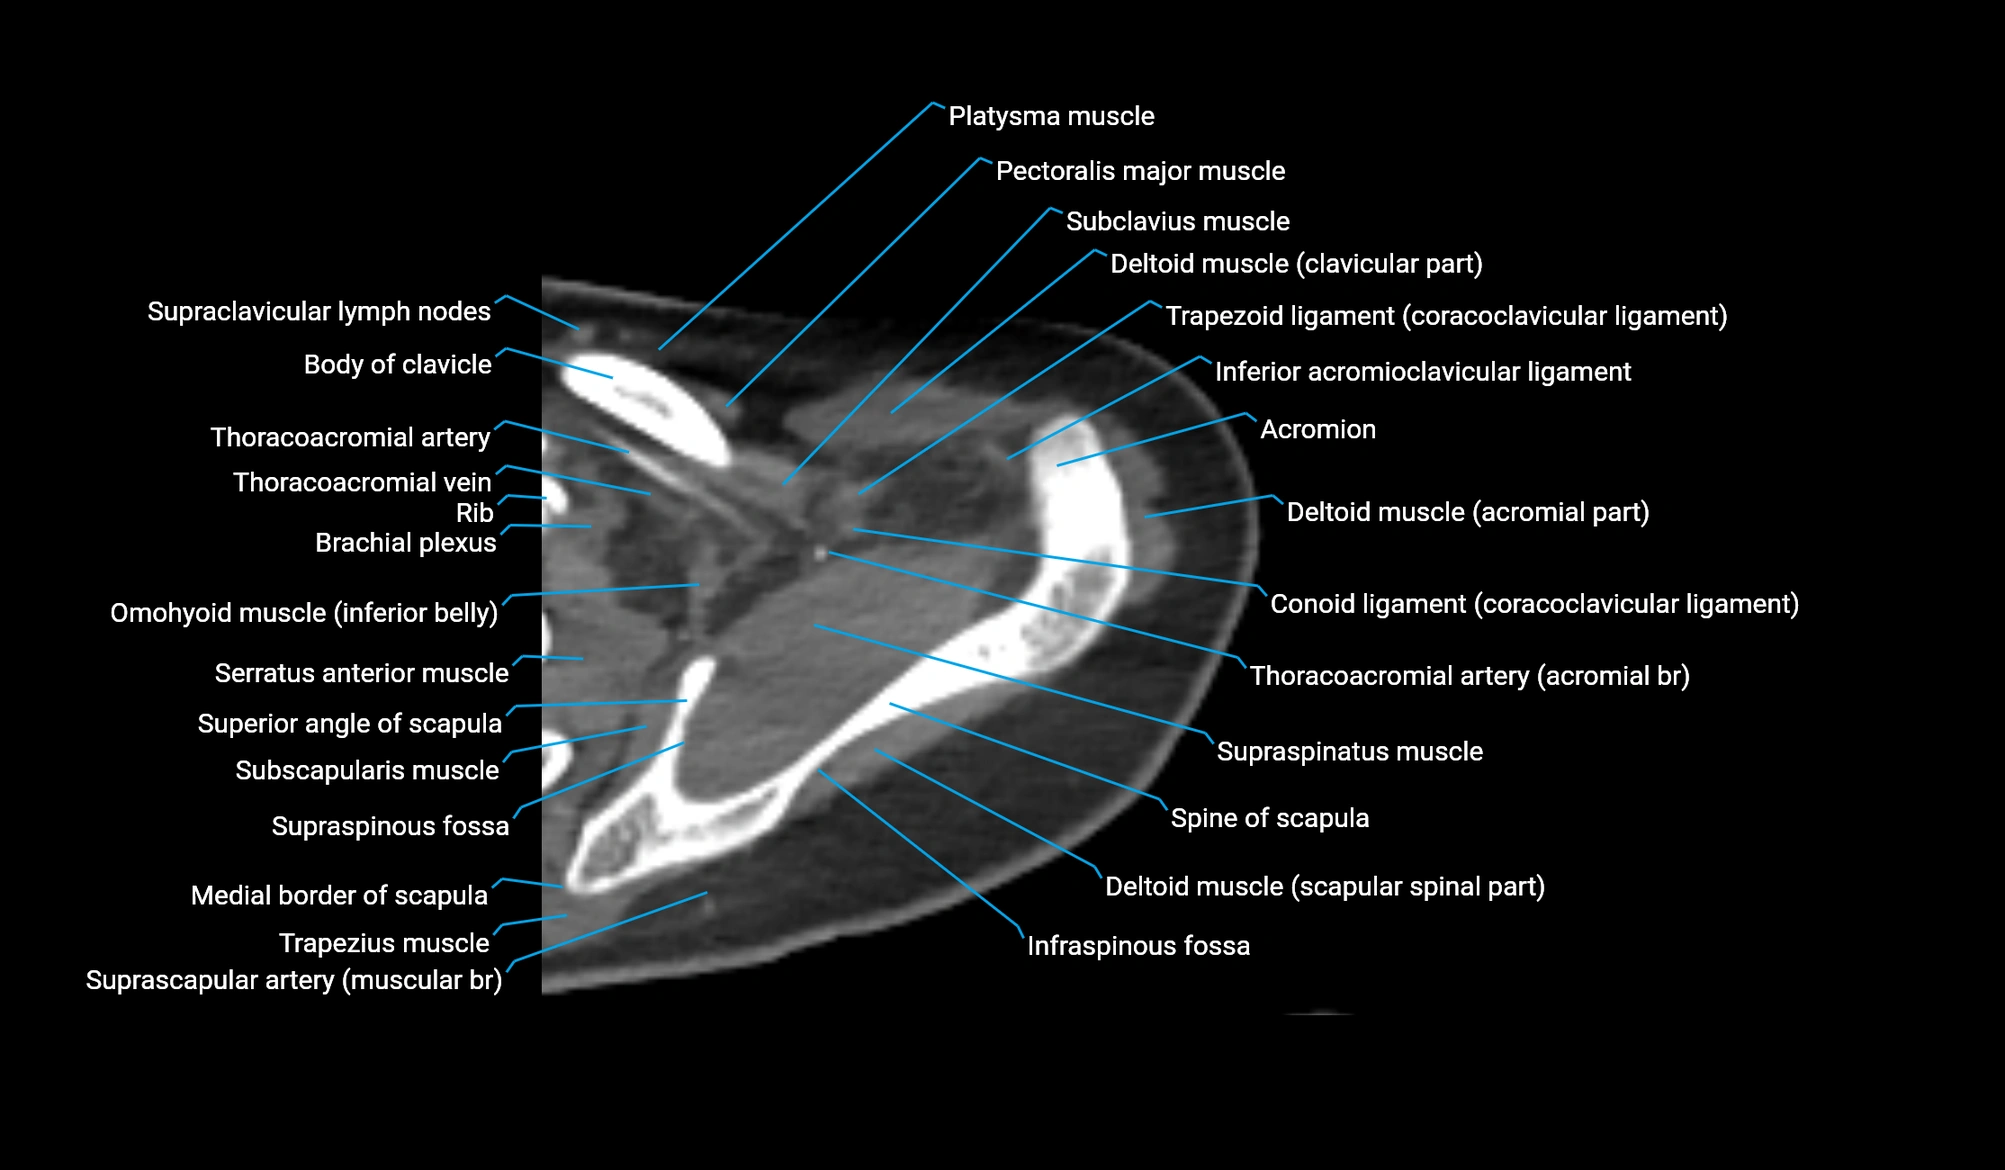

- Acromial end of clavicle

- Brachial plexus

- Clavicular part of deltoid muscle

- Conoid ligament

- Coracoacromial ligament

- Inferior acromioclavicular ligament

- Inferior belly of omohyoid muscle

- Infraspinatus tendon

- Infraspinous fossa

- Pectoralis minor muscle

- Shaft (body) of clavicle

- Subclavius muscle

- Subscapularis muscle

- Superior angle of scapula

- Supraspinatus muscle

- Trapezoid ligament